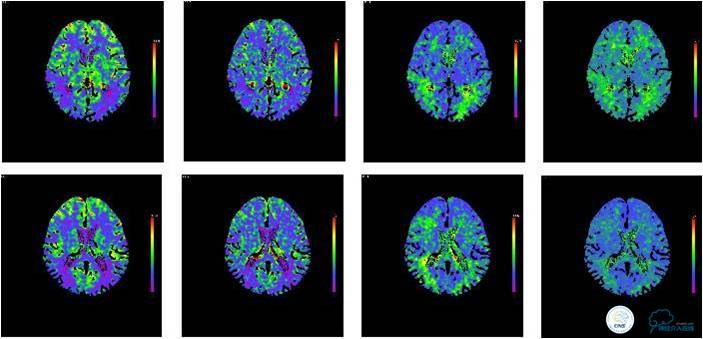

图4:患者入院后灌注CT提示未见明显低灌注区域。

患者入院后,完善颅内CTA(图1)及血管造影(图2~3)检查,发现右侧颈内动脉颅内段闭塞,右侧大脑前动脉依靠左侧颈内动脉系统通过前交通动脉供血,右侧大脑中动脉供血区则依赖于右侧大脑前动脉(ACA)软脑膜代偿供血,左侧大脑中动脉闭塞,依靠一少见血管代偿供血,该血管起自左侧大脑前动脉A2段起始部,代偿供应左侧大脑中动脉供血区。由于该患者灌注CT(图4)未见明显低灌注区,遂给予患者抗血小板、降脂及控制危险因素治疗出院。出院后电话随访未再出现过上述症状。

综上所述,这是一例少见的大脑中动脉闭塞后由RAH代偿供血的病例,由于患者的灌注CT显示灌注尚可,暂时未对患者进行外科干预。